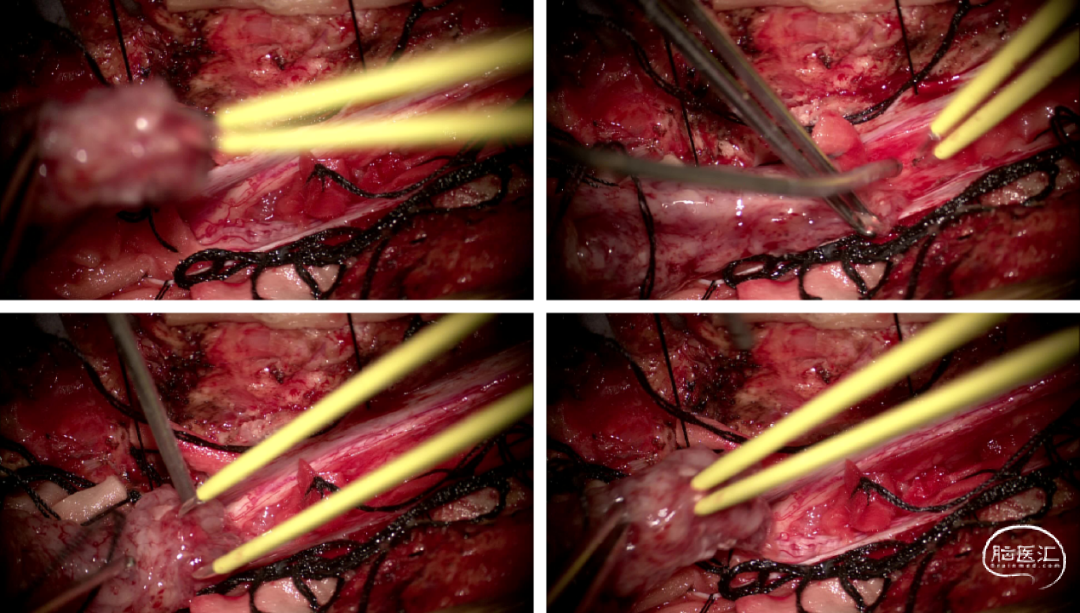

硬脊膜张力高,脊髓向背侧膨出,与脊髓腹侧粘连紧密,肿瘤挤压脊髓,肿瘤边界分离,减少对胸髓的牵拉,降低了术后患者神经功能发生的概率,术后患者肢体麻木症状改善。